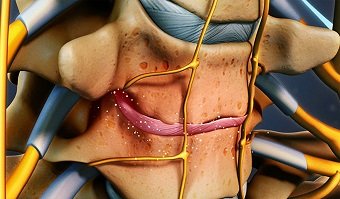

دیسک در بین مهره های گردن یک ساختمان جذب کننده فشار و شوک است . دیسک بین مهره ای معمولاً با افزایش سن پیر میشود. خشک و چروکیده شده و خاصیت الاستیک خود را از دست میدهد. ارتفاع آن کم میشود و همین امر موجب میگردد مهره ها به یکدیگر نزدیک شده و فاصله آنها کم شود. با کم شدن فاصله بین مهره ها فشار زیادی روی مفاصل بین مهره ای وارد میشود که این خود موجب آرتروز یا سائیدگی این مفاصل میشود .

3- هرنی دیسک

یا دررفتن دیسک . در این وضعیت قسمت حلقوی محیطی دیسک (آنولوس فیبروزوس) پاره شده و قسمت مرکزی (نوکلئوس پولپوزوس) از بین شکاف پارگی به بیرون راه پیدا میکند. این قسمت بیرون زده را هرنی یا فتق میگویند. مهمترین مشکلی که در فتق دیسک بوجود میاید اینست که قسمت بیرون زده به اعصابی که در حال بیرون آمدن از نخاع و مهره هستند فشار آورده و همین فشار موجب بروز بسیاری مشکلات از جمله درد اندام فوقانی است .